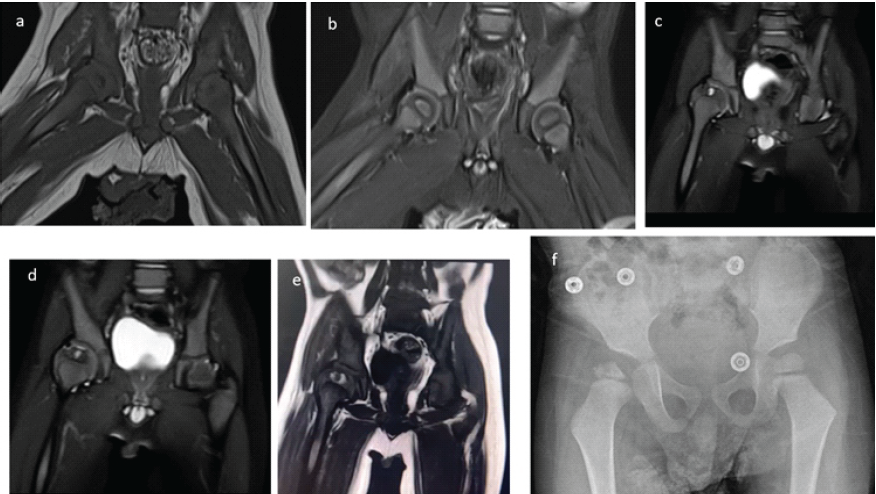

Concomitant microscopic examination revealed the presence of erythrocytes, a few leukocytes, and no detectable microorganisms. Following the exclusion of septic arthritis, joint debridement surgery was deemed unnecessary. The control X-ray in the next morning, revealed a more centralized femoral head. However, following the aspiration, there was a significant and sustained decline in hemoglobin levels. Consequently, the patient was referred to our Level I hospital for further evaluation and intervention, where specialized hematology and pediatric orthopedic services are available to address the situation. Upon arrival at our pediatric department, the patient was administered erythrocyte suspension and fresh frozen plasma. The prolonged aPTT, together with MRI findings were suggested to be indicative of hemarthrosis and the hemorrhagic nature of the aspirated joint fluid, raised strong suspicion for a hematological disorder, particularly hemophilia. Additional laboratory tests were subsequently conducted. During this period, the patient was evaluated in our department, where a Pavlik harness was applied for joint stabilization. Laboratory results revealed von Willebrand factor (VWF) at 98%, factor IX at 63%, and a markedly low factor VIII level of 4.4% (normal range: 70–150%), thereby confirming the diagnosis of hemophilia. In light of the joint bleeding episode, primary prophylaxis was initiated with 250 units of concentrated plasma-derived factor VIII. The pediatric infectious disease specialist recommended a continuation of antibiotic therapy for 20 days with vancomycin and ciprofloxacin until a definitive diagnosis was established to rule out septic arthritis. On the 20th day after aspiration, a follow-up MRI was performed, revealing that the femoral head had centralized with no effusion present (Fig. 3a and b).

Figure 3: (a) T1-weighted coronal magnetic resonance imaging (MRI) showing the hip reduced to its normal position at post-operative 3 weeks. (b) Coronal short tau inversion recovery MRI showing both femoral heads in place without any signs of avascular necrosis. (c and e) T2-weighted coronal MRI obtained at post-operative 3 years, showing a cystic lesion with a surrounding hyperintense signal on the T1-weighted coronal image. These findings are indicative of hemophilic arthropathy (subchondral cyst caused by recurrent intra-articular hemorrhages leading to hemophilic arthropathy). (f) X-ray at post-operative 3 years showing the extent of deformity.